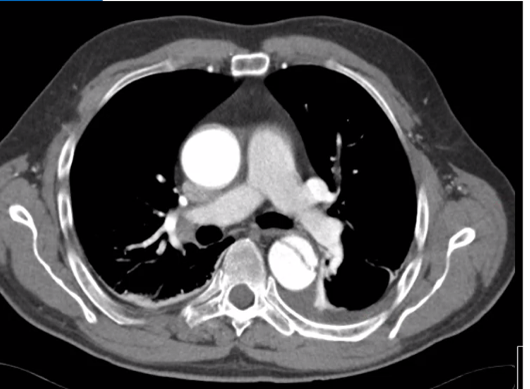

Vad ser du på bilden?

Aortadissektion

Falsk lumen på denna bild